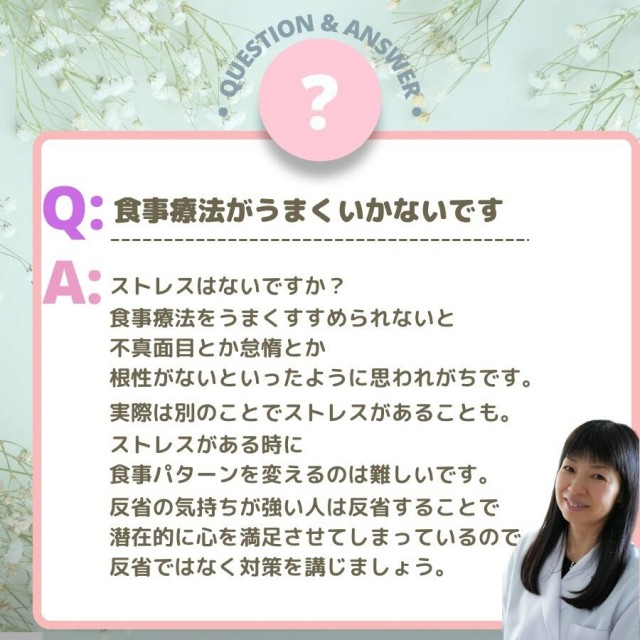

妊娠中の食事

妊娠中の食事

妊娠中の食事